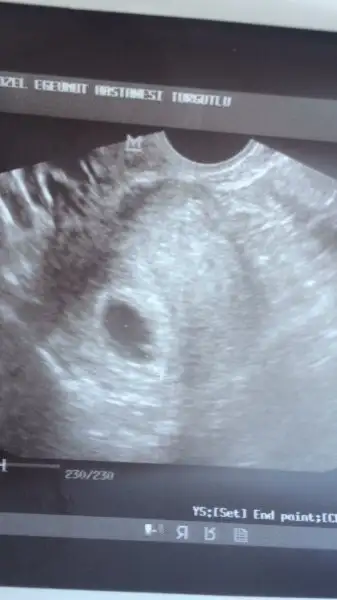

Hayırlı olsun canım darısı kalp arışı bekleyen herkesin başınaKızlar Günaydın hepinize çook teşekkür ederim. Sesini açmadı ama direk kalbindeki hareketi gördüm. Allahım mucize gibi. Valla ilk bebeğimde hemen anneliğimi hissedememiştim. Doktor karnıma ultrason şeyini koydu direk ve bebeğimi gördük . Hemencik annem diyiverdimDarısı sizee en kısa zamanda . Bide doğuma 24 ocak dedi Hayırla sağlıkla gelsinler inşallah.